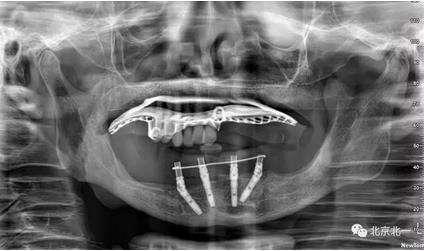

圖一至圖六明顯看出右側(cè)頦孔位于牙槽嵴頂。很清晰看出頦孔區(qū)的U型形狀。

圖七:采用A04技術(shù),拔除下頜余留牙,修整骨平面。在頦孔前方傾斜植入兩枚植體,避開頦孔。減少懸臂。前牙區(qū)植入兩枚直的植體。完成即刻修復(fù)。一日得牙,缺牙后多少年來都沒有吃過蘋果的滋味,到種植牙時(shí)代,想吃什么就吃什么, 我的健康我做主。